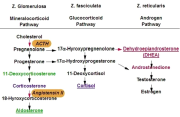

| 15:18, 4 בנובמבר 2012 | אדרנל1014.png (קובץ) |  |

132 קילו־בייטים | Motyk | 1 | |